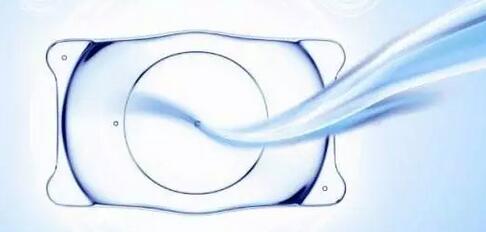

3ICL晶体植入术--高度近视的福音

ICL无需改变眼睛本身的结构,对角膜无损伤,适合高度近视、干眼症、角膜偏薄等近视族, 范围广,可 300-2000度近视、600度以内散光,弥补了激光 1200度以上超高度近视领域的空缺。